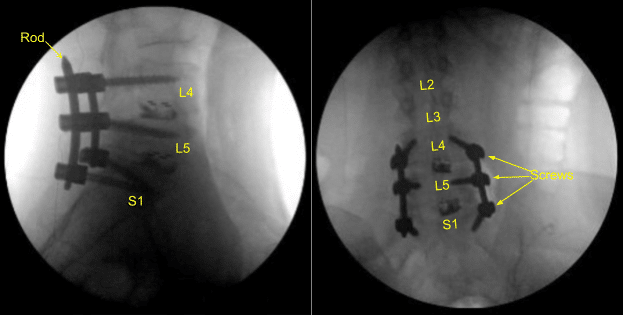

The wound was irrigated clear. Bovie monopolar and Cobb elevators were used to follow the Wiltse approach, divided the fascia and exposed the spinal hardware on the right side. Gelpi self-retaining retractors were placed. The L4, L5 and sacral pedicle screw locking caps were removed with the appropriate driver and anti torque device.

The titanium rod was then removed with curettes and rod gripper. The right S1 pedicle screw was noted to be loose and was removed easily with a screwdriver. The hole was then palpated with a ball-tip feeler probe and was noted to have a ventral breach.

No cerebrospinal fluid was seen to egress from this area. Surgiflo hemostatic matrix was placed. Next, the right S1 pedicle screw starting point was exposed with the Bovie monopolar at the inferolateral aspect of the L5-S1 facet joint and just inferolateral to the sacral ala.

Intraoperative CT scan was obtained, and data was transferred to the neuronavigation computer and accuracy was verified. Neuronavigation techniques were used to cannulate the right-sided first sacral segment which was then palpated for breaches and measured at the depth of 35 mm. A 6.0 mm navigated tap was used to thread the cannulation. It was again palpated for breaches and a 7.5 x 35 mm titanium pedicle screw was placed with good bony purchase and tightness.

Next, the patient was re draped and a second intraoperative CT scan was obtained showing correct positioning of this pedicle screw. Neuromonitoring signals were stable throughout. Next, the L5-S1 transverse process and ala were decorticated with a high-speed drill for the arthrodesis after exploring the fusion and failing to identify bony arthrodesis and bone graft.

Again, a precut-precontoured titanium rod was placed across the pedicle screw tulips from L4 to S1 and secured with the locking caps which were tightened with a torque and anti torque device. Morselized bony allograft was placed across L5-S1 on the right side for the arthrodesis.